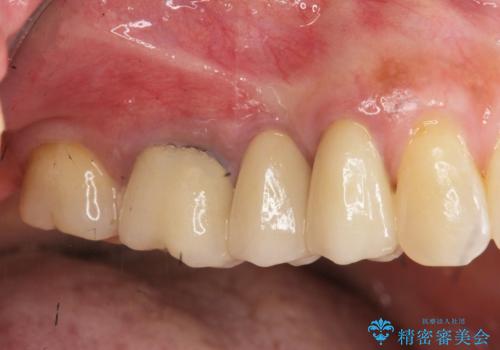

前歯の変色 セラミッククラウンによる審美回復

担当医 大元洋佑

古くなったセラミッククラウンのやりかえ